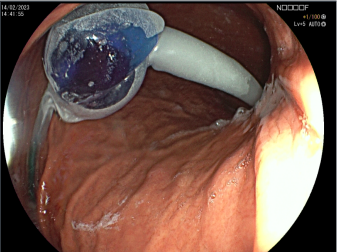

Extirpación de Tumores -

Mucosectomía

Extirpación de Tumores Incipientes

Esófago - Estómago - Cólon